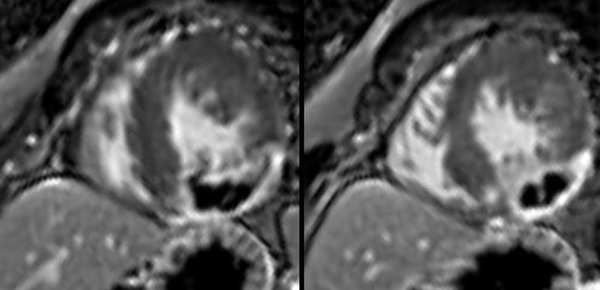

Combined CMR and PET/CT give synergistic information in patients with granulomatous cardiomyopathy